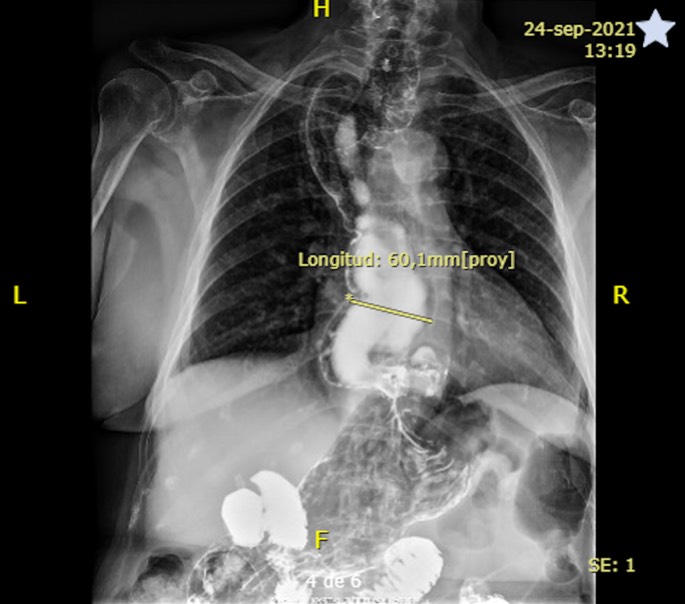

Se completó el estudio con esofagograma (septiembre 2021) donde se evidenció una gran dilatación del esófago de unos 6 cm, sugerente de trastorno motor esofágico, con herniación de la funduplicatura al mediastino posterior. El vaciamiento del esófago era aceptable en bipedestación, pero en decúbito se observaban movimientos de vaivén del bario en el esófago.